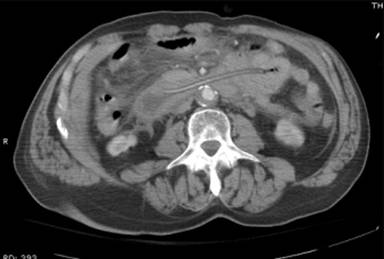

A 79-year-old African American male with past medical history of stroke, diabetes mellitus, hypertension, chronic obstructive pulmonary disease, Alzheimer’s dementia, atrial fibrillation and bilateral below knee amputation was sent from a nursing home for evaluation of nausea, an episode of non-bloody vomiting, and epigastric pain. The patient had no history of prior alcohol abuse. Medications included enalapril, warfarin, a multivitamin, calcium, albuterol, prednisone and donepezil. On examination he was stable and was not in acute distress. Mild tenderness was noted in the epigastrium. In the nursing home, a Foley catheter had been inserted in place of the PEG-tube which had been accidentally pulled out few days before. The hemoglobin was 18.8 g/dL (reference range: 14.0-17.5 g/dL), white blood cells count 13,800 mm-3 (reference range: 4,400-11,000 mm-3), platelet count 196,000 mm-3 (reference range: 150,000-450,000 mm-3), blood urea nitrogen 22 mg/dL (reference range: 6-20 mg/dL), serum creatinine 1.3 mg/dL (reference range: 0.5-1.2 mg/dL), and glucose 188 mg/dL (reference range: 70-110 mg/dL). Liver enzyme tests, serum triglyceride and serum calcium were within normal limits. Serum amylase (1,448 U/L; reference range: 0-100 U/L) and lipase (1,565 U/L; reference range: 7-60 U/L) were elevated. An ultrasound of the abdomen did not reveal gallstones, sludge or biliary dilatation. A CT scan of the abdomen with oral contrast showed findings suggestive of acute pancreatitis. A Foley catheter balloon was identified in the second portion of the duodenum (Figure 1). A diagnosis of acute pancreatitis was made. The patient was started on i.v. fluids and pain medications. The Foley catheter was replaced with a 20 French replacement PEG-tube. A gastrograffin study was done to confirm the placement. The nausea, vomiting and abdominal pain improved and the serum amylase and lipase returned to normal. The patient had no further episodes of pancreatitis. No other cause for acute pancreatitis could be identified.

Figure 1. CT scan of abdomen showing Foley catheter balloon in the duodenum. Case#1. |